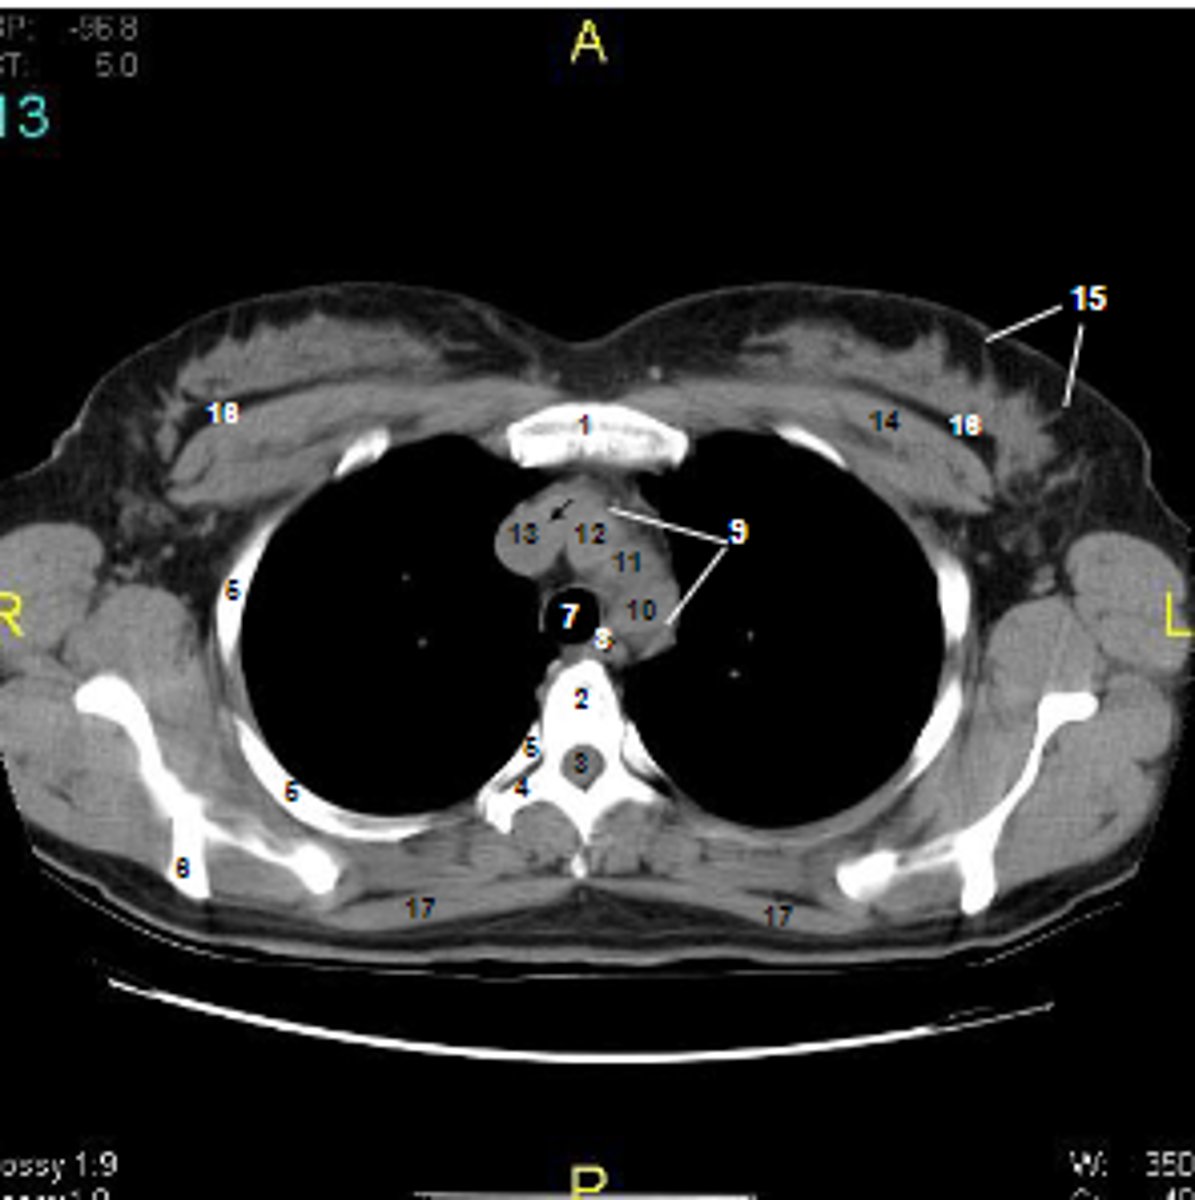

1

at what number is the sternum

2

at what number is the vertebral body

3

at what number is the vertebral canal/ spinal cord

4

at what number is the transverse process of vertebra

5

at what number is the rib

6

at what number is the spine of scapula

7

at what number is the trachea

8

at what number is the esophagus

9

at what number is the arch of aorta

10

at what number is the left subclavian artery

11

at what number is the common carotid artery

12

at what number is the brachiocephalic trunk

13

at what number is the superior vena cava

14

at what number is pectoralis major

15

at what number are Cooper's ligaments

16

at what number is the retromammary space

17

at what number is trapezius